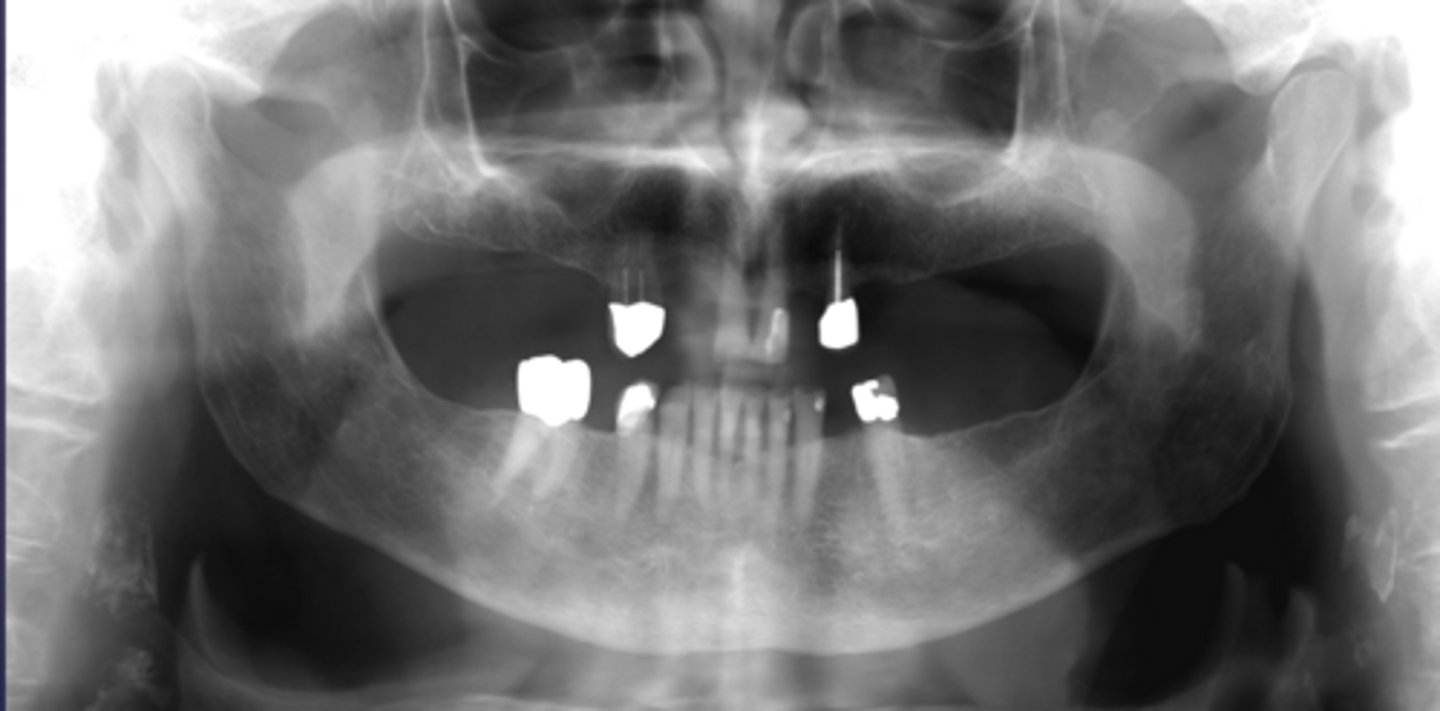

How would you describe the lesion?

- Generalized reduced trabecular bone density in maxilla and mandible

- The teeth appear to be more prominent with the lacking osseous support. Lamina dura not very distinct in multiple locations.

- There are two large defined radiolucencies located in the posterior mandible

- The right side radiolucency is causing thinning of the inferior mandibular cortex and displacement of inferior alveolar canal

- There is wispy septae noted within

- The left mandibular lesion appears to be defined but scooped out along the alveolar crest

What category would this lesion be part of?

Systemic

What would be a differential diagnosis for this lesion?

Hyperparathyroidism (brown tumor)